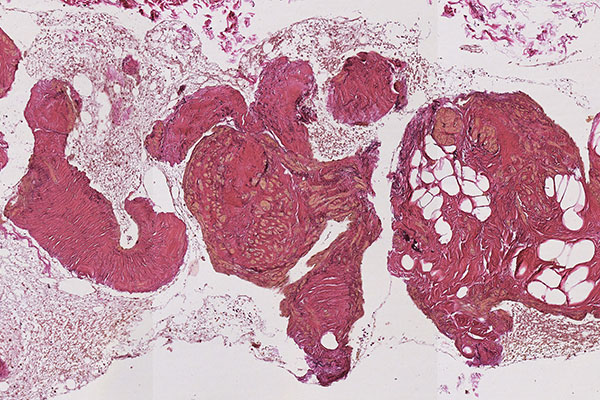

Histopathological section; hematoxylin & eosin (HE) stain, 90x magnification of the punch cylinder. Punch cylinder showing parts of venous malformation with densely packed, irregularly configured large-caliber venous vessel parts. These do not appear tubular as in a normal mature vessel, but as if the vessels are "everted". The lumen looks solid and blood is all around the outside.

Histopathological section; hematoxylin & eosin stain (HE), 160x magnification of the punch cylinder. Here it is clear to see that the irregular, blood-filled spaces of the venous malformation are not solid, but are "voids" partially filled with erythrocytes. The endothelial lining corresponds to the outer border of the visible lesion.